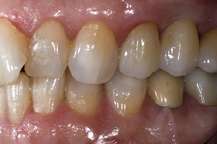

These are usually called prosthetic implant abutments. These abutments can be made from a variety of materials, such as titanium, surgical stainless steel and gold. More modern abutments are now also made from zirconia,[3] which is a white ceramic, to better complement the aesthetics of a dental implant restoration. The two images to the right show a ceramic abutment and the ceramic crown bonded to it. The images to the right show how a ceramic abutment can enhance a ceramic crown by giving it a more lifelike appearance. Ceramic abutments have to be used with care, however, since their compressive strength is nowhere near that of titanium, gold or other noble metals. Most clinicians feel more comfortable using a metal prosthetic abutment in the posterior molar areas, due to the increased masticatory forces present in these areas.